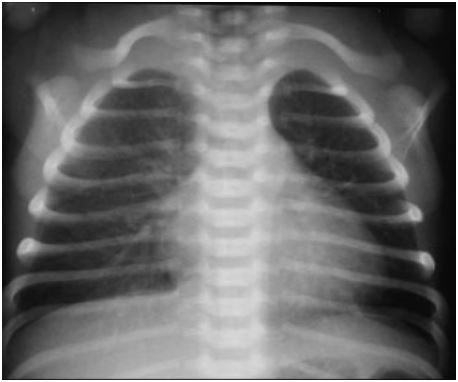

RN a termo/pré-termo tardio, nascido de cesárea eletiva, com quadro de desconforto respiratório nas primeiras horas de vida (taquipneia, tiragem, retração, BAN, cianose, gemência), Rx com congestão hilar, aumento da trama vascular, liquido cisural, cardiomegalia e hiperinsuflação….

Diagnóstico, fisiopatologia, tratamento e prevenção?

Taquipneia transitória do RN

Retardo na absorção do liquido pulmonar (síndrome do pulmão úmido)

FR: cesárea eletiva em atermo/pré-termo tardio

Tratamento: Resolução espontânea em 72h, suporte, oxigenio <40%, não faz diurético

Prevenção: evitar cesáreas eletivas, TP reduz o risco de taquipneia